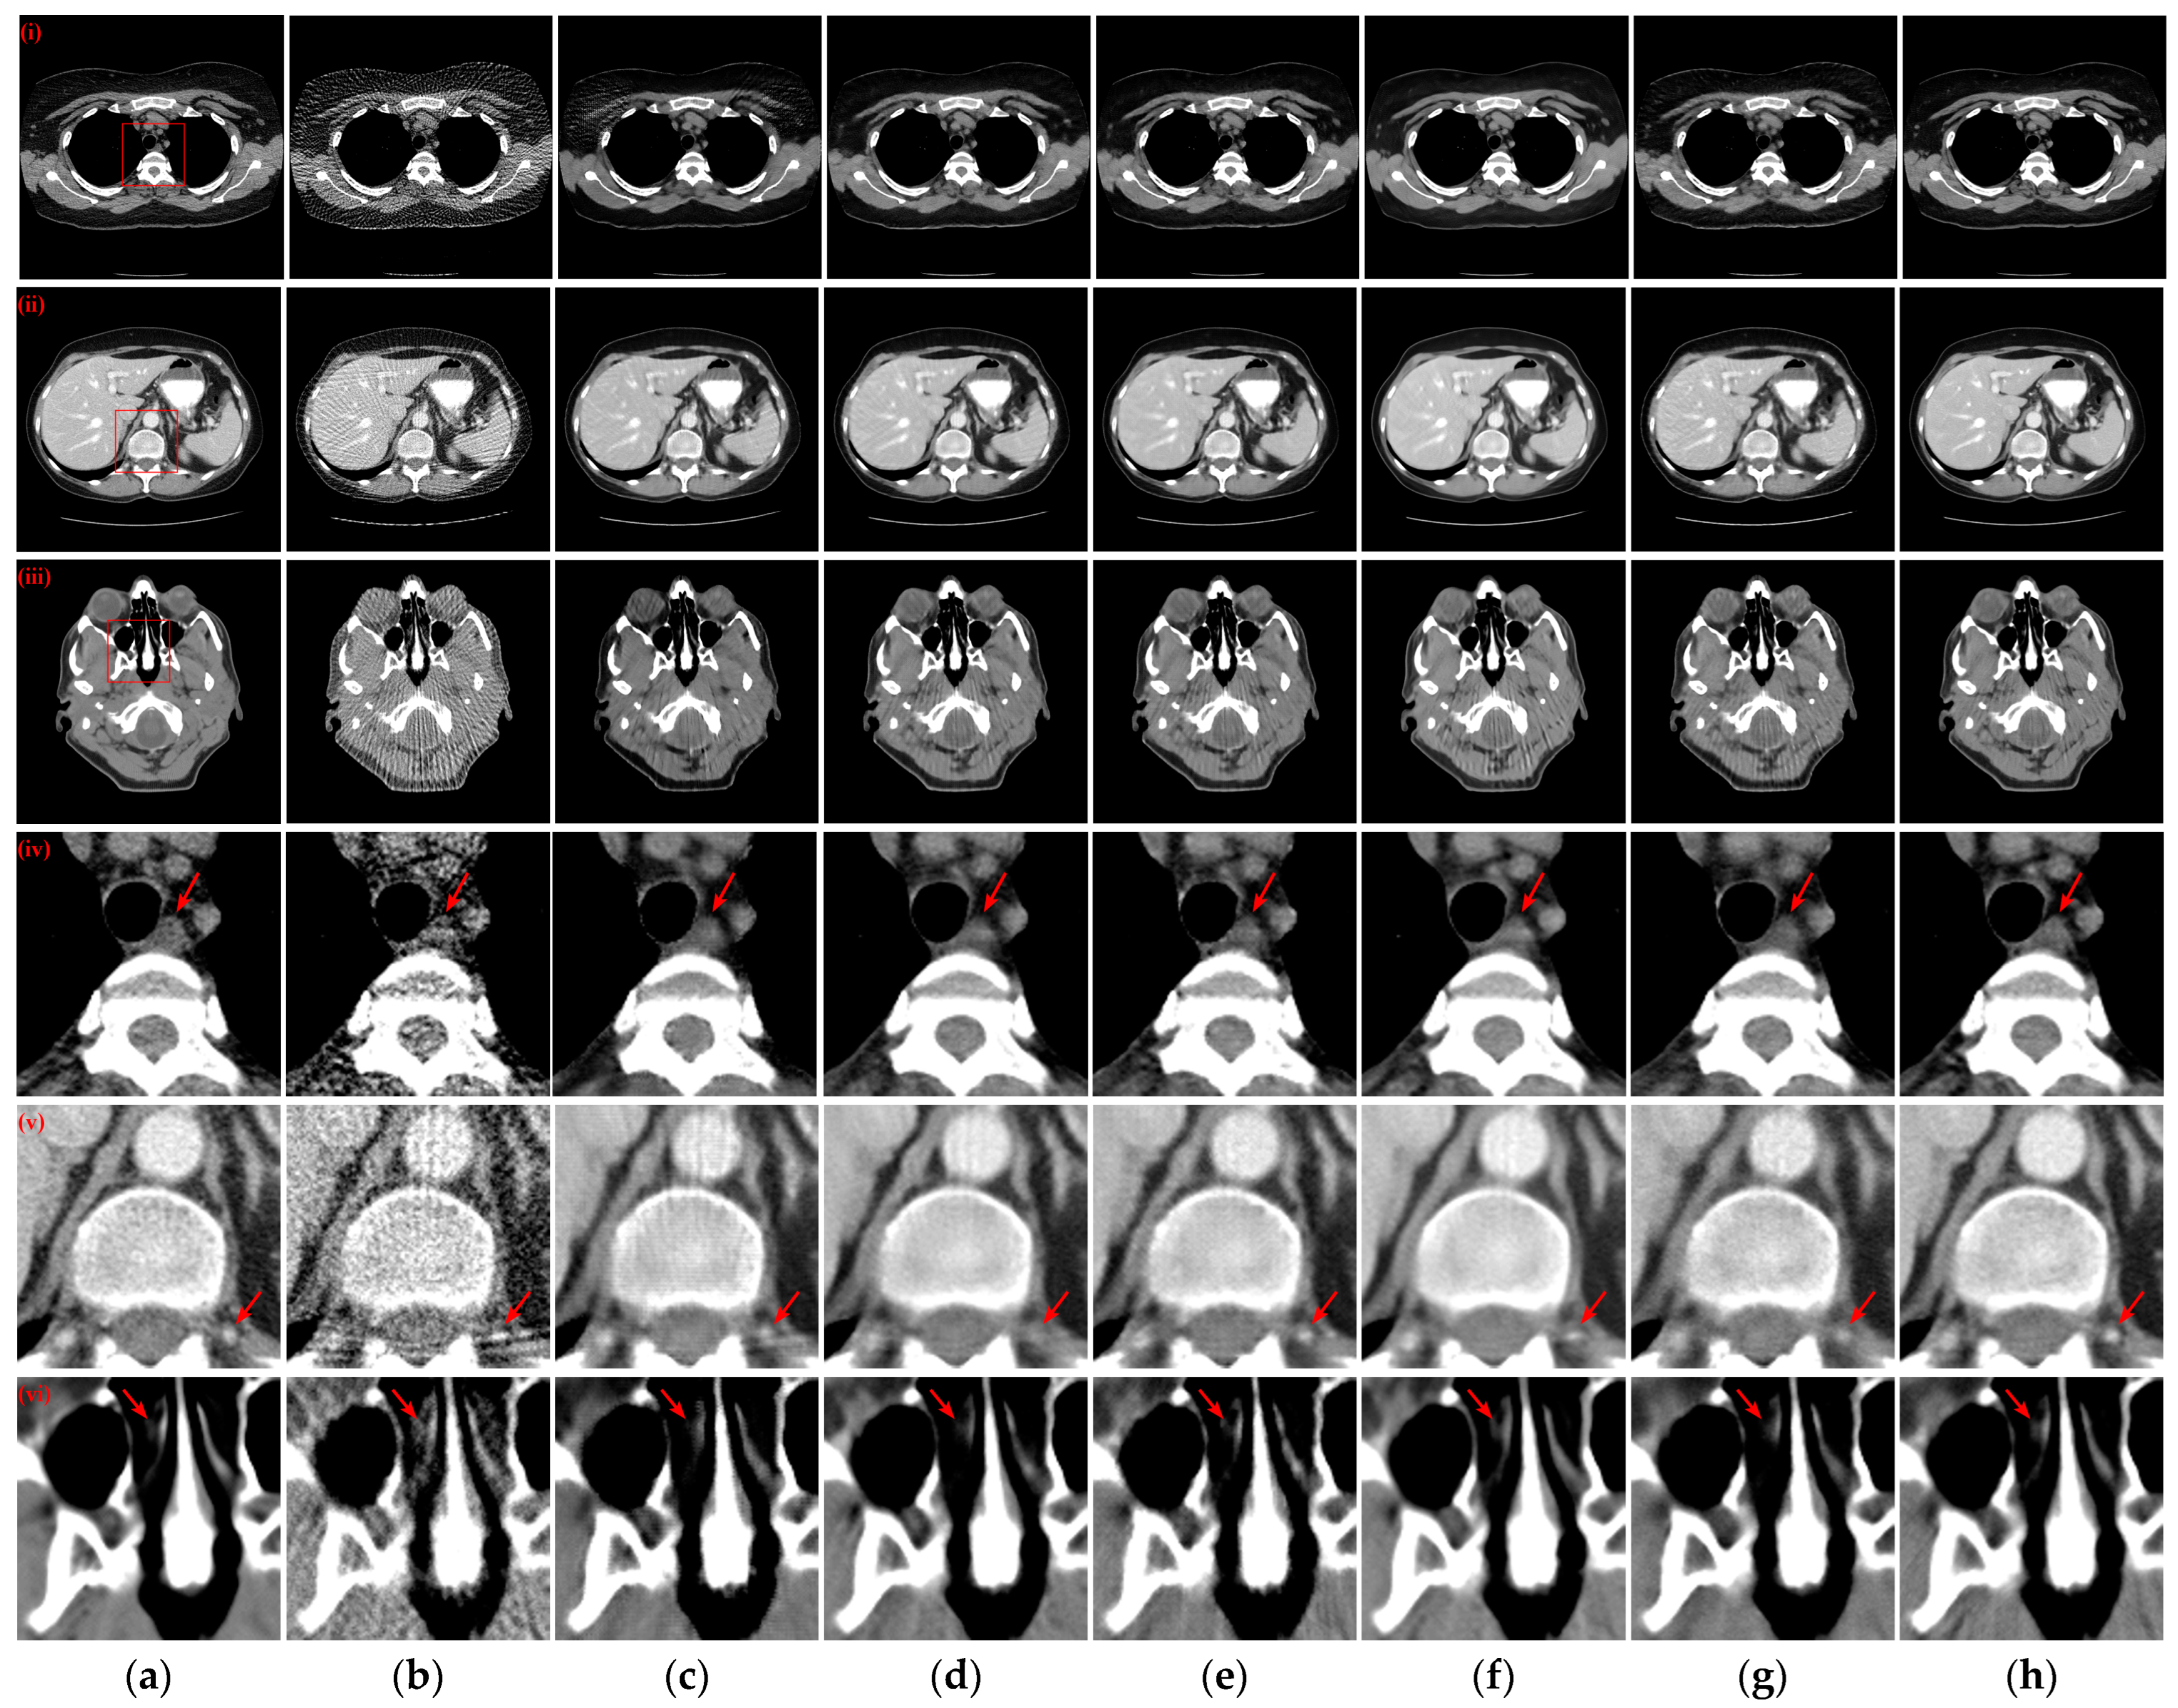

3.2. Qualitative Evaluation